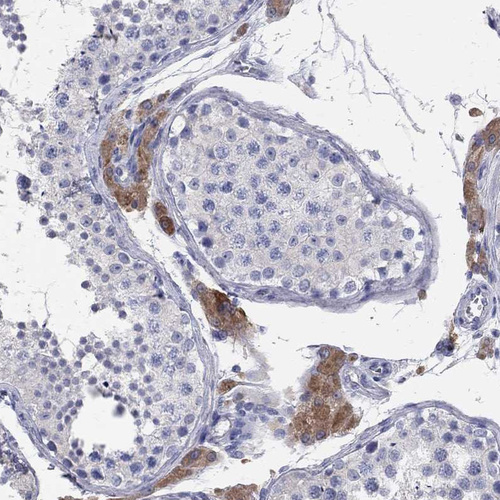

Immunohistochemistry analysis in human liver and lymph node tissues using HPA040199 antibody. Corresponding AOX1 RNA-seq data are presented for the same tissues.